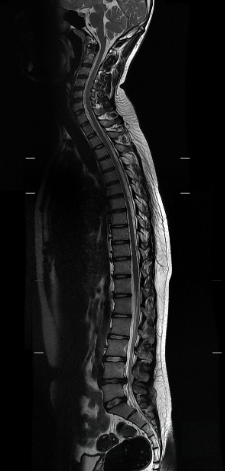

It’s all Spine

A 38-year-old male presents with acute on chronic low back pain. On arrival, he has a fever, 3+/5 strength of the right leg, and 5/5 strength on the left. Sensation to light touch in his bilateral lower extremities is intact with a positive straight leg test bilaterally.